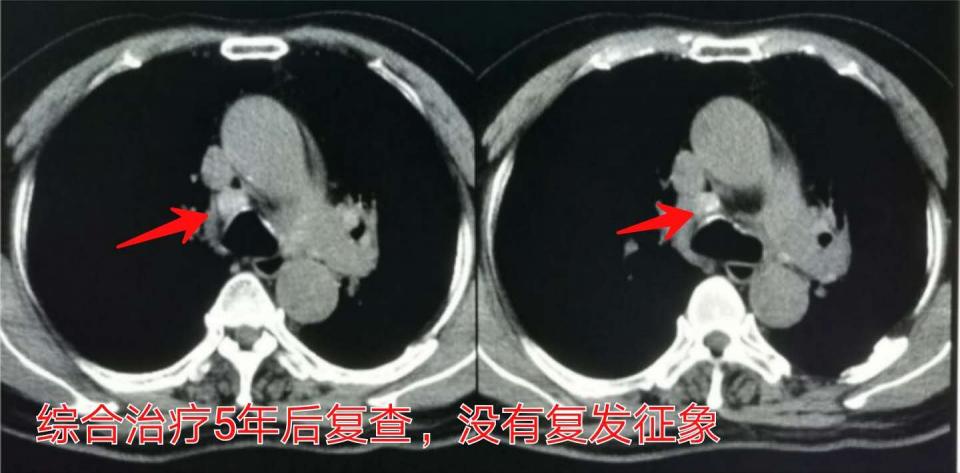

1.60岁的男性,胸闷咳嗽2月,确诊为肺癌并广泛淋巴结转移:

五年后复查,没有复发征象(做过化疗,没有做手术):